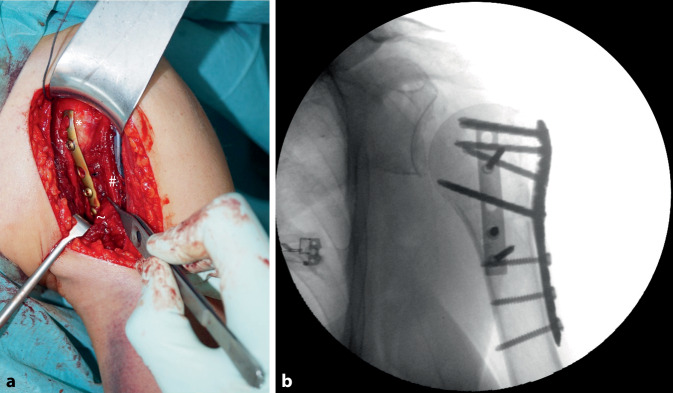

Abstract Image